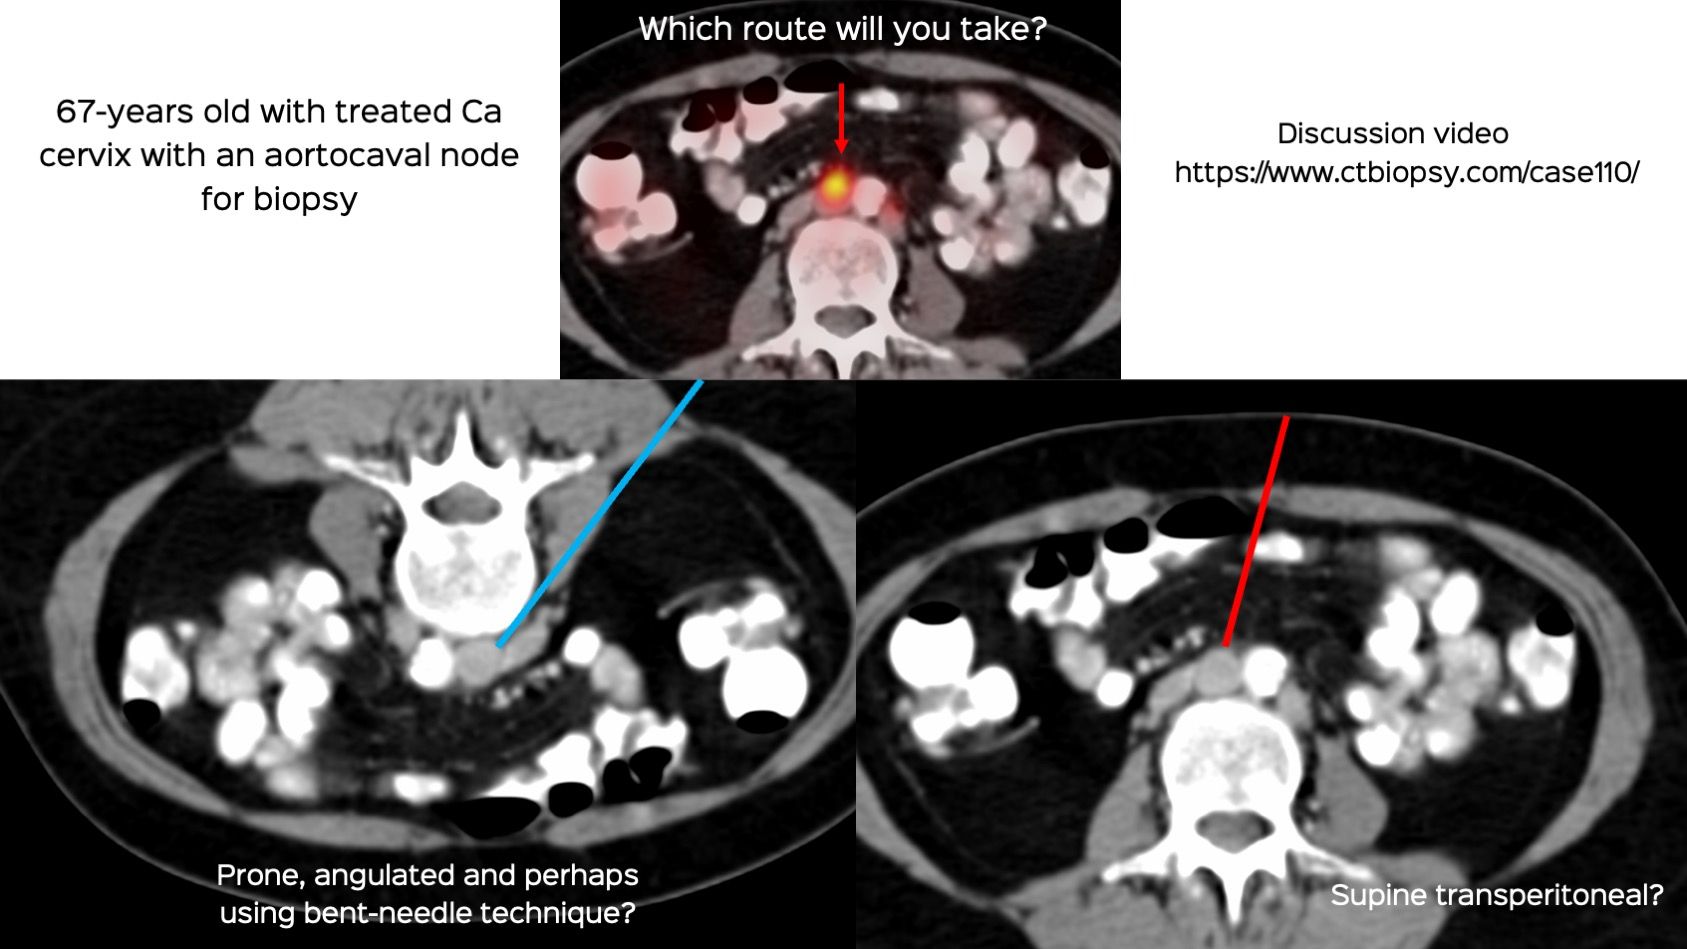

Case 110: Retroperitoneal Aortocaval Node Biopsy

Bhavin Jankharia - 21 November 2022